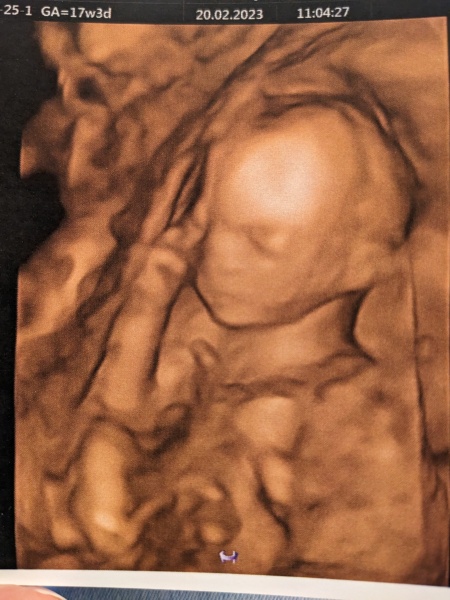

Found out I’ve got an anterior placenta so not expecting movements for a while. Anyone the in the same boat? Also got to see the baby on the 4D scan thingy as part of my private NIPT appointment which was fun. The sonographer wasn’t able to tell the sex because the baby was in the wrong position so waiting on the blood test results.

Aww this is so cute! My 4D scan looked terrifying 😂

@squirrelnutkins1 the 4D scans do look slightly like melted cheese 😂